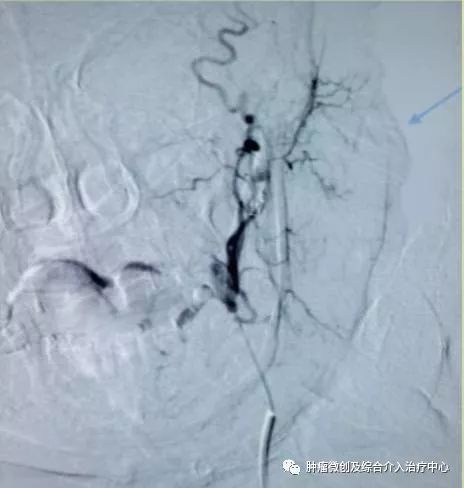

(介入栓塞病变血管后,DSA示肿瘤病变血管栓塞好,血管走向清晰,出血停止)项目介绍:头颈部良、恶性肿瘤临床常见,其良性见于鼻咽纤维血管瘤,恶性者见于鼻咽、鼻窦癌,颈部转移性肿瘤等; 传统止血治疗疗效有限,给患者及家属带来极大的精神压力,介入手术栓塞病变血管可达到确切的止血效果,并致病变缺血萎缩。04急性肺栓塞介入手术治疗